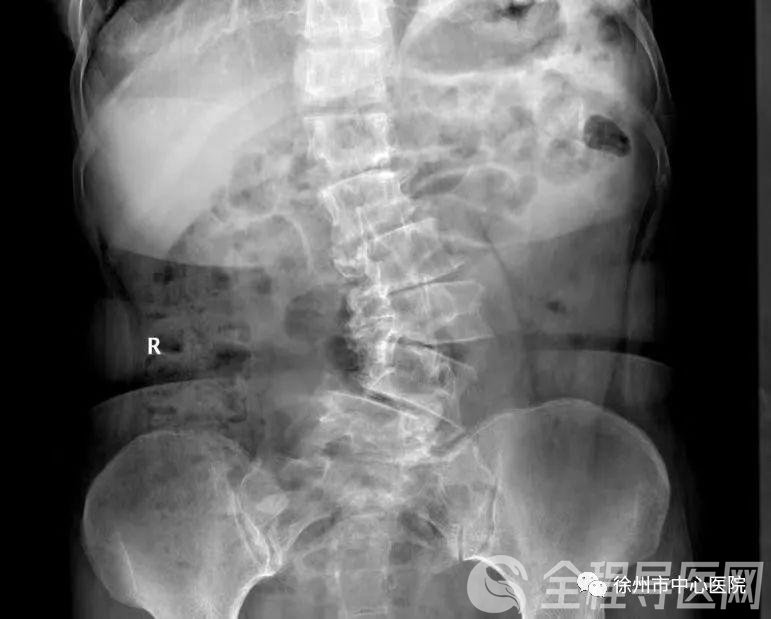

中国脊柱侧弯的发病率为2%~3%,多在青春期后(10岁以后)。近年来,过早脊柱侧弯(0~10吊)的概念被提进去。脊柱侧弯已成为继瘦削和远视之后中国儿童和青少年的第三大杀手。自2019年起,国度卫计委在全国在校生经常出现病及肥壮影响要素监测中,将脊柱意外笔挺作为检测目的,笼罩400多个地级市、200多万在校生。

刘海英引见,脊柱侧弯对儿童和青少年的危害体如今两个方面:一方面,重大影响好看,孩子会出现心思和精气疑问;另一方面,会侵害孩子的神经系统,甚至压榨脊髓,造成不可行走,并惹起心肺配置意外,从而影响寿命。他提示,在生存中,家长应及时关注孩子的体态(肩、胸、背、腰线),或让孩子弯下腰,看能否一侧背高,另一侧背低。假设无心外状况,请及时到医院就诊。

近年来,因脊柱侧弯来医院就诊的中小在校生有参与的趋向。他们中的大少数是家长,发现孩子穿的衣服少了,肩膀显著高下不平,后背不平。去医院审核后,他们被诊断为脊柱侧弯。然而,很多患者发现侧弯曾经是s形了,或许侧弯曾经到达40度以上。他们年龄太大,错过了激进治疗的最佳机遇。有些人自愿须要启入手术治疗,这对儿童来说是十分有害的。